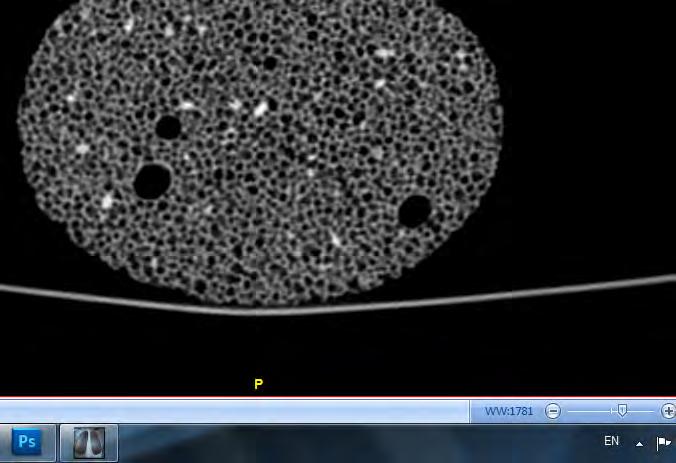

Following our interest in natural artefacts and thier cellular organization, a method of analysing and investigating these systems was required. Typically, architects and designers utilize 3D-scanning sonar devices to obtain a three-dimensinonal computer model of complex objects or natural artefacts. However there are several technical limitations within 3D-scanning and the results only provide an exterior morphological view or reconstruction of the scanned object. What we were rather interested in was the interior structure of the object and the organization of cells, their variation and the reason behind these variations. Furthermore, the interest was in relating natural models which contain aspects of redundancy and randomness for variation within the morphology, to the mathematical geometrical models and comparing aspects of each.

The field of Radiology within the medical discipline is considered to be one of the most advanced in terms of imaging and tomography. Computed Tomography scans also known as CT were developed to produce sectional images through a body or organism for diagnosis purposes. The technology uses X-ray images within a single axis of rotation to image slices which can be reconstructed to three-dimensional images.

For our research purposes and investigation of natural cellular systems we undertook a number of computed tomography scans for various natural artefacts. The CT scans were done at the Imaging Department in St. Mary’s Hospital, London. Senior Radiographer: Shirley Featherstone

The equipment at the facility is a Philips Brilliance 64 and 256-slice scanner. The scans provide slices at an interval of 0.4mm in two directions, coronal and transverse. The digital resolution of the slices are at 500x500 pixels. The format of these slices are DICOM which is the common format within the medical Industry. The images are monochrome and based on an Xray where the image is entirely about the contrast received from the scan.

For our research purposes and investigation of natural cellular systems we undertook a number of computed tomography scans for various natural artefacts. The CT scans were done at the Imaging Department in St. Mary’s Hospital, London. Senior Radiographer: Shirley Featherstone

The equipment at the facility is a Philips Brilliance 64 and 256-slice scanner. The scans provide slices at an interval of 0.4mm in two directions, coronal and transverse. The digital resolution of the slices are at 500x500 pixels. The format of these slices are DICOM which is the common format within the medical Industry. The images are monochrome and based on an X-ray where the image is entirely about the contrast received from the scan.

Throughout the analysis and use of the DICOM slices, multiple softwares were used for both viewing the images and reconstructing the slices to a three-dimensional model. For viewing purposes MicroDicom and Agnosco Dicom Viewer and RadiAnt DICOM viewer. For the reconstruction of the slices to obtain a geometrical 3D model, InVesalius 3.0 was utilized.

During the arrangements for the Computed Tomography scans, we prepared a range of natural artefacts which could be analysed to provide potential knowledge of natural cellular systems and the variety within them. The objects scanned included: corals, tree bark, sea horse, sea stars, lava stone, pumice stone, cork and spider crab. The size of most objects was small and did not exceed 100mm in length.

The resolution of the slices obtained from the scan is sufficient to provide an observation towards the structure that would be visible by human eye if the object is sliced. The slices however were not at a resolution where microscopic structures or features could be examined.

Therefore, the resolution of the performed CT-scan was ideal for certain objects, and for other less relevant for our analysis purposes. This depends on the scale of cells or pores in relation to the object. Shown below, are images taken by the scanner of each object scanned, in addition to a selected slice which shows the object most clearly.

The two objects that were of main interest were the coral and pumice stone, this is due to the clarity of the structure within the given slice resolution where the cells can be observed throughout the slices. These two were taken for further investigation, specifically in terms of the variations they hold within the different cells.